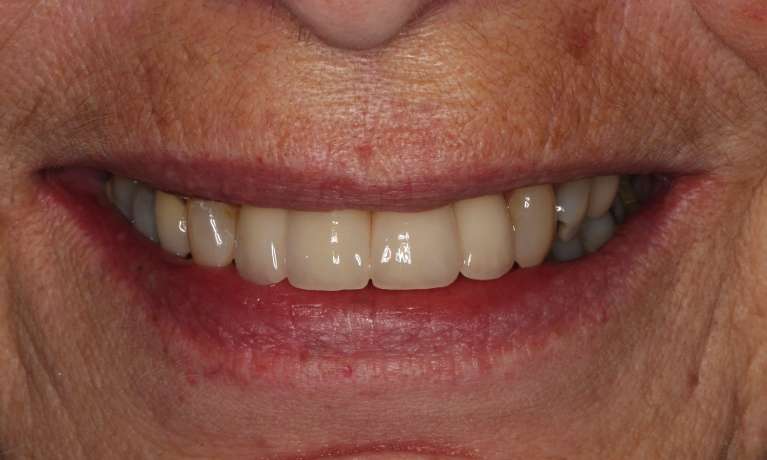

This adult patient had heavily restored discolored and defective upper front teeth. Their upper front four teeth were rejuvenated with new crowns to give the finished smile.